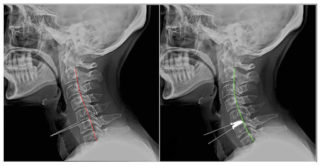

Первый вариант встречается чаще. При смещении позвонков на обычном снимке врач ставит диагноз – остеохондроз. Единственный способ подтвердить или опровергнуть его – рентгенография при максимальном разгибании и сгибании шеи. При сгибании шеи линия, соединяющая задние части всех позвонков, должна оставаться ровной и гладкой. При нарушении плавности диагностируют смещение.

Рентген с функциональной пробой включает 3 снимка: задняя проекция в позиции лежа или сидя и 2 боковых в положении максимального изгибания шеи и максимального же разгибания. Боковые снимки лучше делать стоя или лежа.

Очень важно занять правильную позу. Напряжение в одной части хребта обязательно сказывается на другом участке позвоночника, поэтому для каждого положения разработана специальная поза.

Боковой снимок в позиции стоя делают так: пациент боком соприкасается с вертикальной стойкой, наклоняется вниз как можно ниже, опускает руки на пол, голова свободно опущена, колени зафиксированы.

Рентген в момент максимального разгибания проводится так: больной стоит боком, сильно выгнувшись в пояснице, голову откидывает назад, кисти рук на затылке. Если такая позиция причиняет боль, пробу делают со специальной латерографической приставкой на спине.

Применение рентгена с функциональными пробами заметно увеличивает информативность обследования.